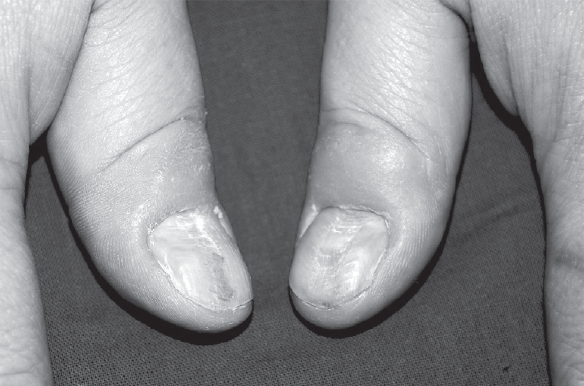

An increase in the number of patients with psychodermatological manifestations and the identification of a certain comorbidity during the course of diseases in patients with a dermatological profile makes us take a fresh look at this problem. Psychodermatology is one of the relevant and, at the same time, the least studied areas of modern medicine, which is at the junction of psychiatry and dermatovenereology. Psychiatry and psychotherapy studies the inner world of a person; Dermatovenerology deals with the diagnosis and treatment of diseases of the human skin and its appendages, and psychodermatology combines these two sections of medicine. In the modern world, as a result of increasing the amount of incoming sensory information, accelerating the rhythm of life, the action of harmful environmental factors, a person can be subjected to excessive psycho-emotional stress, leading to the development of mental disorders. Often it is skin rashes that are an objective manifestation of such disorders. Early diagnosis of psychodermatosis and signs of obsessive-compulsive pathology in sick people contributes to the timely identification of the category of people at risk of psychotic reactions and mental illness. This is especially true for young patients. Against the background of hormonal changes in the body, the crisis of adolescence, the increased educational load on them at school, the destroyed institute of family and marriage, an overabundance of sensory information and physical inactivity, the incidence of psychodermatosis throughout the world, including in our country, is increasing.